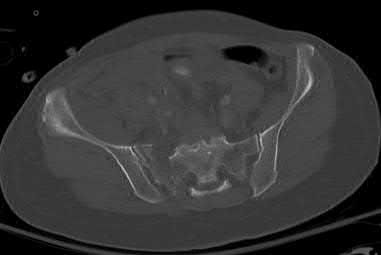

A 65-year-old female presents with the injury seen in Figures A and B after a motor vehicle collision. She is hemodynamically unstable and undergoes emergent pelvic supra-acetabular external fixation followed by laparotomy. She is now hemodynamically stable and cleared for surgery. She has no evidence of neurologic deficit on examination. Which of the following factors is a relative contraindication to open reduction and plating of her posterior pelvic injury from an anterior approach?

An anterior approach to the sacroiliac (SI) joint is indicated with displaced SI joint dislocations that cannot be reduced with closed or percutaneous techniques. One contraindication to anterior exposure of the SI joint is comminuted sacral fracture patterns.

Posterior pelvic ring injuries that are unable to be reduced by closed techniques may require open reduction via anterior or posterior approaches. Relative contraindications to anterior approach include comminuted sacral fractures, morbid obesity, iliac wing external fixation, and ipsilateral diverting colostomy. In the presence of a comminuted sacral fracture, aggressive medial dissection would be required and would place the L5 nerve root at risk.

Simpson et al describe their initial results with open reduction and internal fixation of the SI joint via an anterior exposure in a series of 16 patients. They note that sacral alar comminution is a contraindication to the anterior approach

Answer 2: Prior laparotomy is not a contraindication to open anterior approach if the bowel is in continuity and there is no evidence of wound infection Answer 3: Supracetabular external fixation does not interfere with anterior approach to the SI joint

Answer 4: Anterior pelvic ring injuries such as parasymphyseal fractures do not affect the choice of approach

Answer 5: An ipsilateral proximal femur fracture does not affect the choice of approach